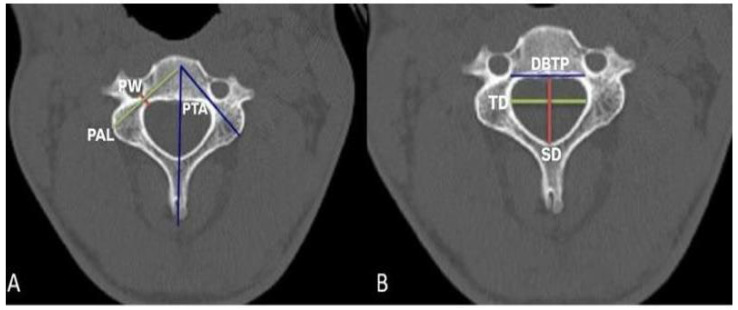

Methods: In our study, pedicle analyses were examined in the subaxial neck vertebrae of a total of 60 patients, 30 male and 30 female, using computed tomography images. In subaxial vertebrae (C3-C7), bilateral pedicle width, pedicle axis length, pedicle transverse angle, sagittal and transverse diameter of vertebral foramen, and the distance between two pedicles were measured.